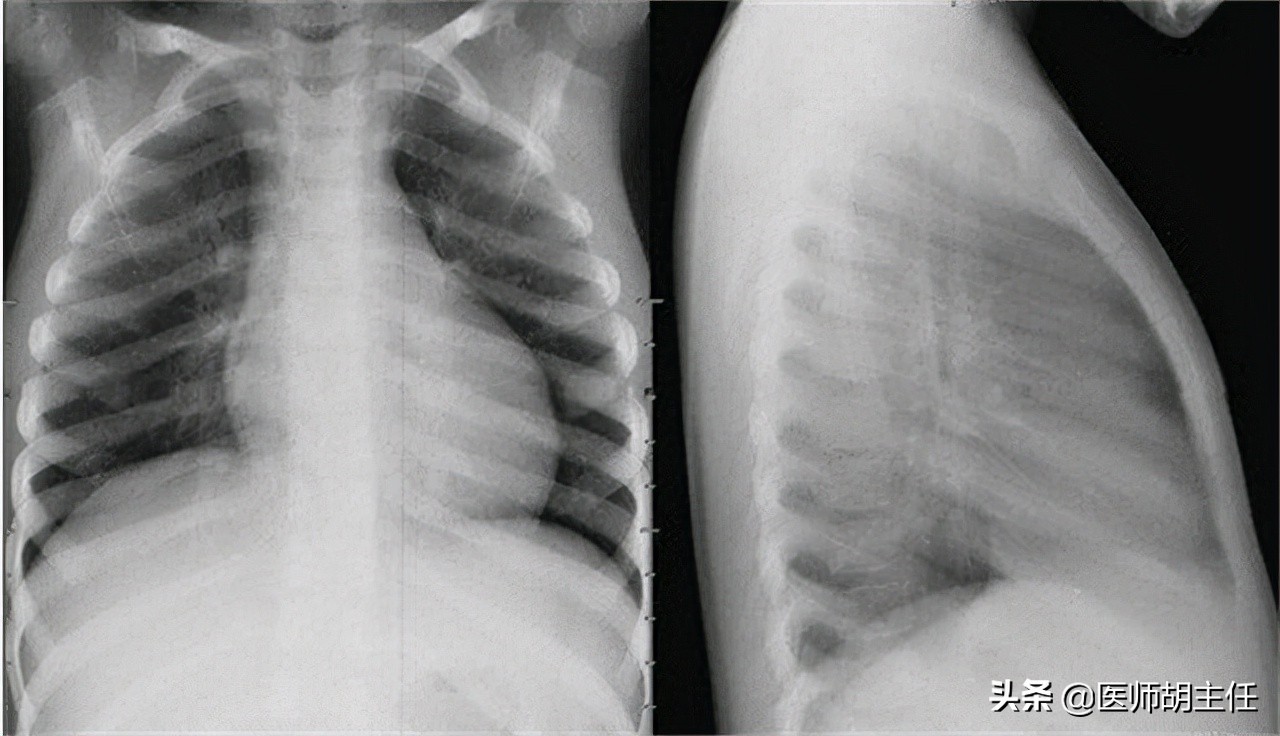

其次,胸片 ,在疾病的早期阶段,X 射线可能无法检测到疾病,因为肺部成像是正常的。当疾病发展到严重阶段时,胸片对于提示慢性阻塞性肺疾病的诊断很有价值,X 光检查结果有助于区分慢性阻塞性肺疾病或其他疾病(如肺结核、支气管扩张、肺肿瘤、肺纤维化)引起的咳嗽、咳痰、呼吸急促……

胸部 X 光片分为 2 种类型:

胸部X光:用于寻找肺部肿瘤,对小病灶效果不大。

计算机断层扫描X线:用于检测肺部肿瘤的大小、位置和侵袭,患者的转移状态,纵隔淋巴结,或在穿透胸壁时帮助指导活检,用于组织病理学诊断。